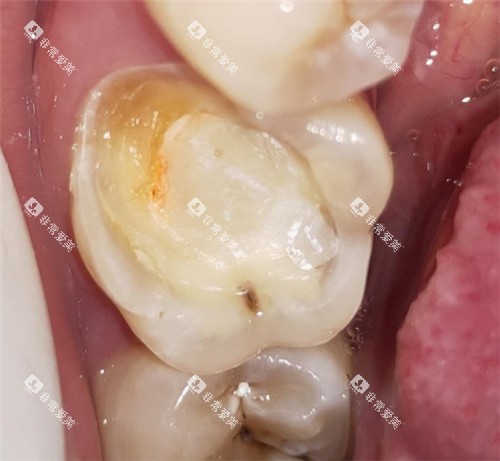

例如,在补牙时,医生会告知患者不同补牙材料的优缺点,让患者根据自己的情况做出选择。

而传统金属牙套在进食时容易残留食物残渣,清洁起来比较困难,长期下去可能会导致龋齿、牙周炎等口腔问题。

在隐形矫正期间,患者需要特别注意口腔清洁,以避免牙齿表面出现脱矿、龋齿等问题。